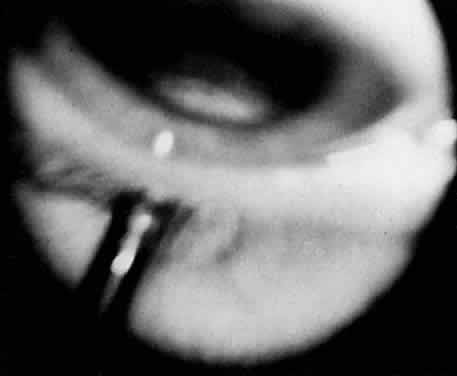

Fig. 6. Pars planitis. Fluorescein angiogram of pars plana membrane showing diffuse leakage indicating neovascularization.

FLUORESCEIN ANGIOGRAPHY AND VITREOUS FLUOROPHOTOMETRY

In pars planitis, fluorescein angiography shows diffuse leakage from the retinal venules and capillaries, without any predilection for the inferior retinal vasculature (Figs. 5 and 6).28 Similarly, vitreous fluorophotometry in patients with pars planitis also shows no predilection for vascular leakage in the inferior peripheral retina.29 These findings suggest that snowbank is most likely a sequela from ocular inflammation, that inferior peripheral retina periphery is not the source of inflammation in pars planitis, and that pars planitis is not a localized inflammatory response of the inferior retina.